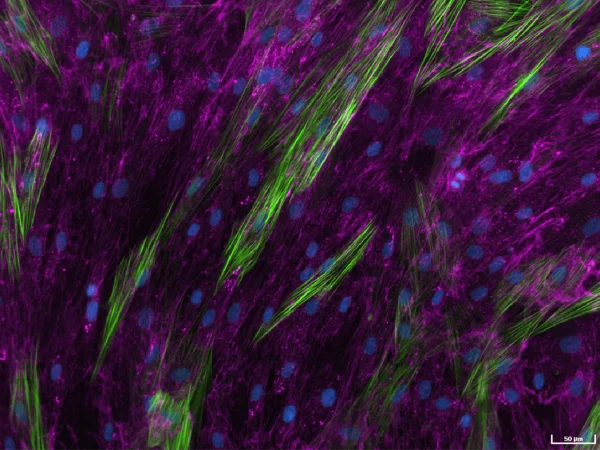

Human lung fibroblasts stimulated with TGF-β1 to detect extracellular collagen I (pink), alpha-smooth muscle actin (α-SMA) (green), and cell nuclei (blue) as a measure of matrix production and fibroblast activation, respectively. Image Credit: Newcells Biotech

Human lung fibroblasts stimulated with TGF-β1 and immunostained to detect extracellular collagen I (pink) and α-SMA (green) as a measure of matrix production and fibroblast activation, respectively. Images captured using ImageXpress Confocal HT.ai imaging system, Scale bar: 50 µM. Image Credit: Newcells Biotech